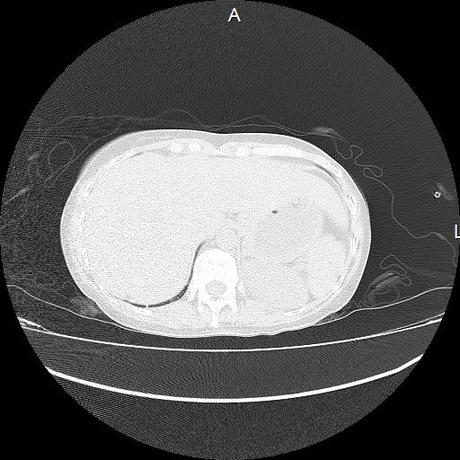

Se realiza volumen de tórax en fase simple, desde los opérculos torácicos hasta los hemidiafragmas, observándose:

El parénquima pulmonar con areas parcheadas difusas en vidrio despulido combinadas con otras areas hipodensas de baja atenuación debidas a atrapamiento aéreo y engrosamiento intersticial y zonas de fibrosis de predominio en lóbulos medios e inferiores de ambos pulmones.

Ambos hemidiafragmas sin evidencia de alteraciones.

En los cortes valorados de abdomen hígado, bazo y páncreas sin evidencia de alteraciones, glándula suprarrenal izquierda con imagen ovalada, bordes definidos, homogénea, mide 11 mm en probable relacion a adenoma.

- LOS HALLAZGOS PUEDEN ESTAR EN RELACIÓN A NEUMOPATIA INTERSTICIAL PROBABLE ETIOLOGIA HIPERSENSITIVA VS AUTOINMUNE/BACTERIANA/FUNGICA.

- PROBABLE ADENOMA DE SUPRARRENAL IZQUIERDA.